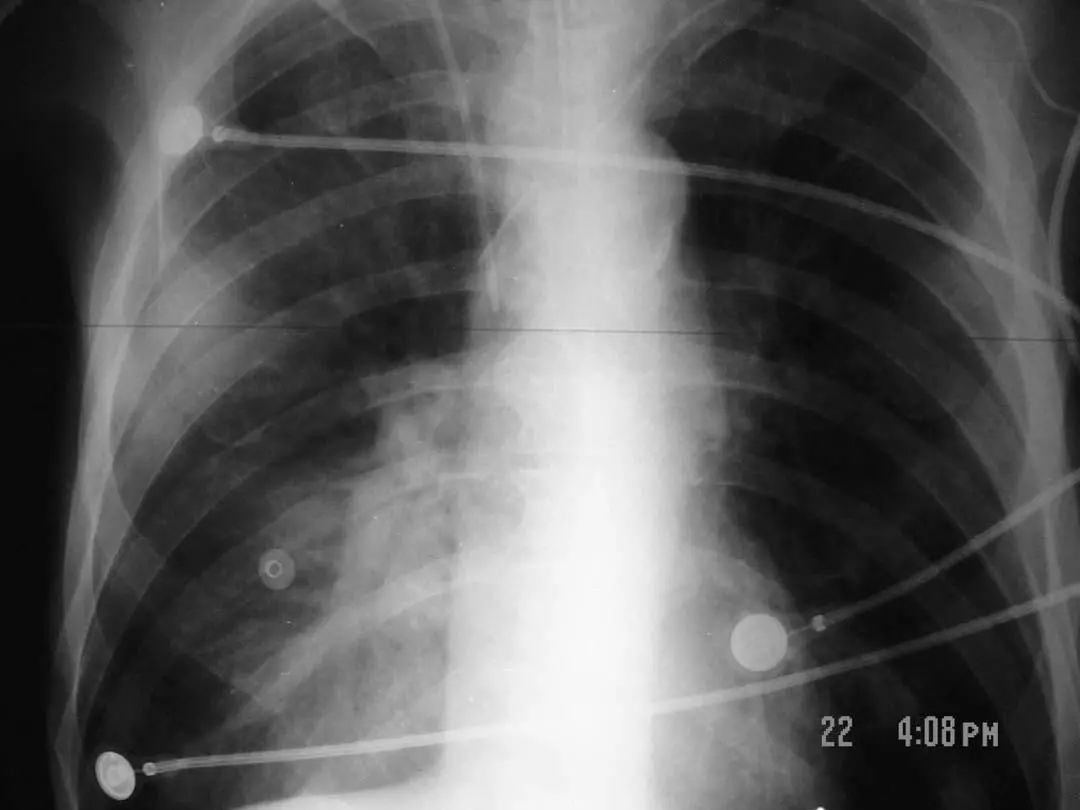

图1.9 49岁肺炎球菌性肺炎患者, 胸部X线片显示左下叶不透明伴胸腔积液。

图1.10 48岁的流感嗜血杆菌性肺炎患者, 胸部X线片显示双侧不透明,主要分布在外周。